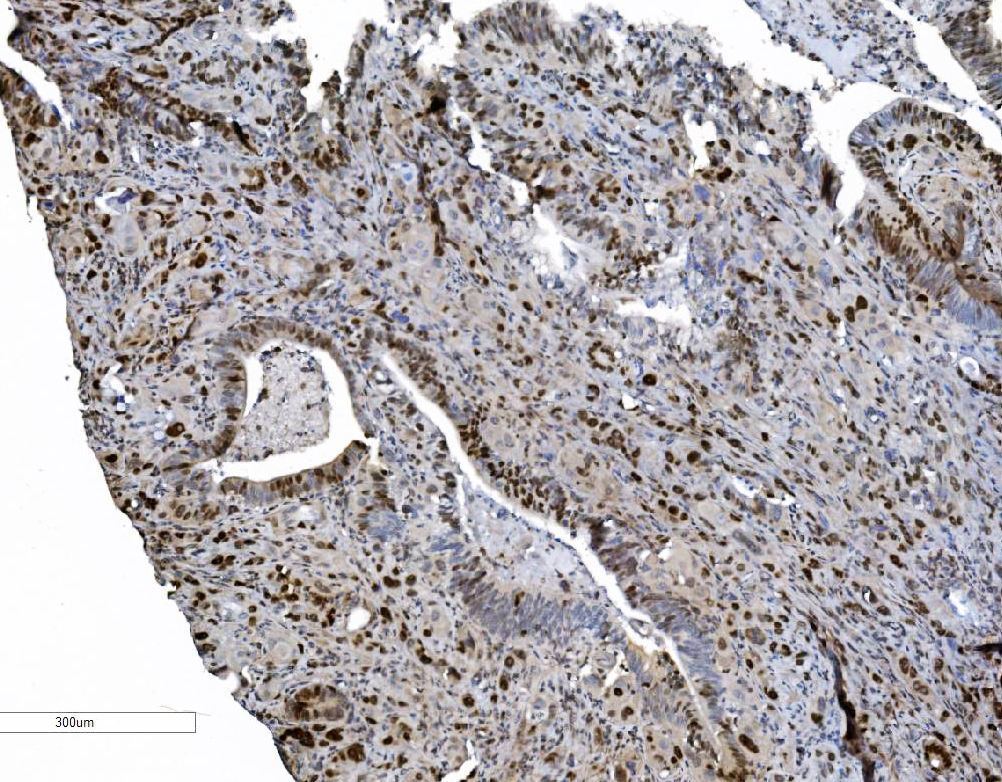

IHC analysis of MCM6 using anti-MCM6 antibody (M02755).

MCM6 was detected in a paraffin-embedded section of human ovarian serous adenocarcinoma tissue. Biotinylated goat anti-mouse IgG was used as secondary antibody. The tissue section was incubated with mouse anti-MCM6 Antibody (M02755) at a dilution of 1:200 and developed using Strepavidin-Biotin-Complex (SABC) (Catalog # SA1021) with DAB (Catalog # AR1027) as the chromogen.